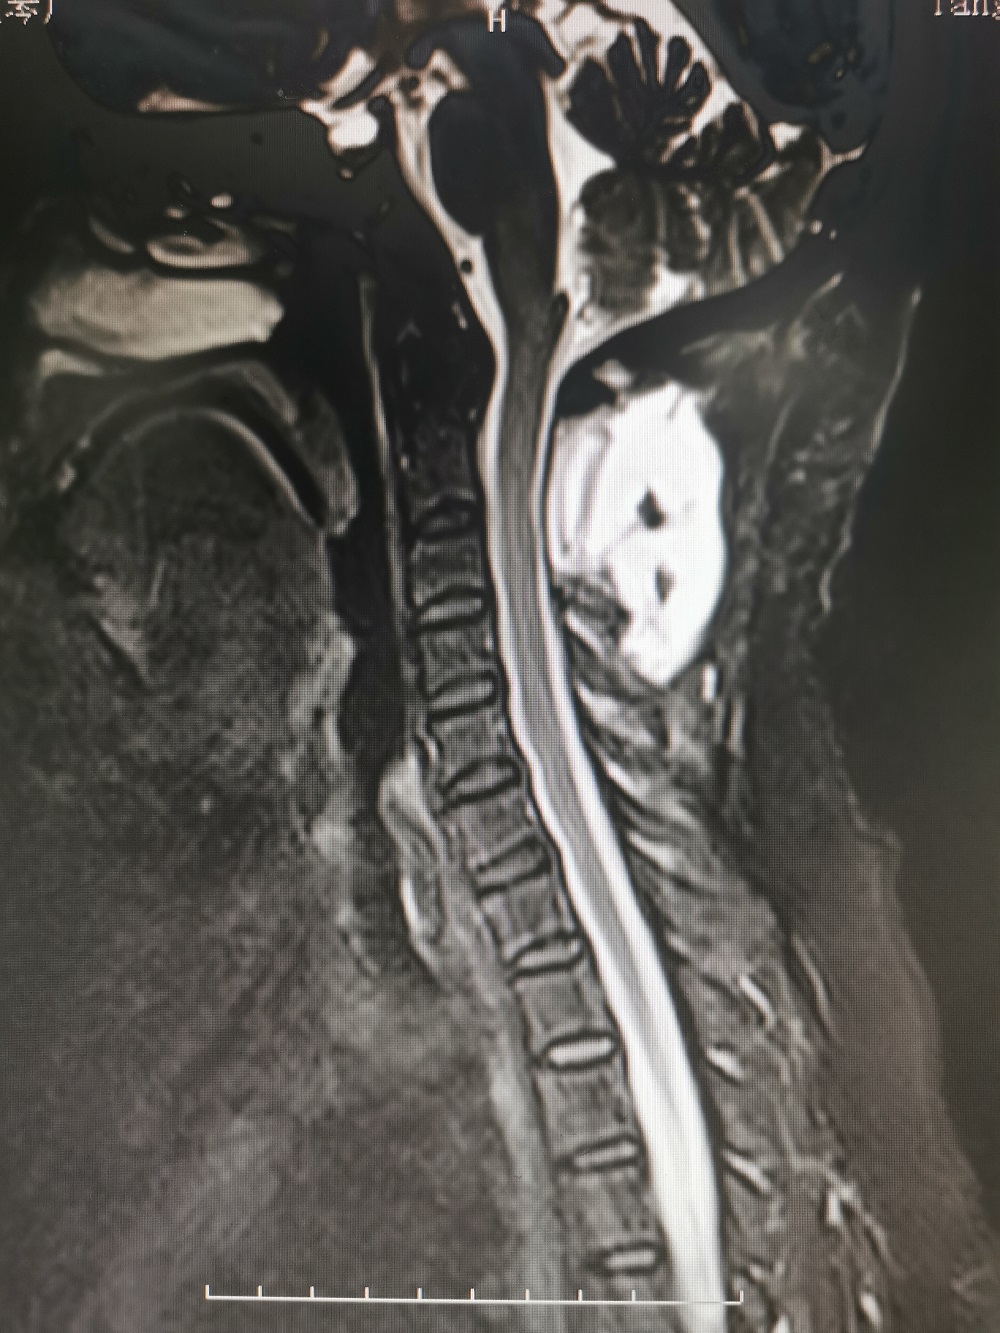

结果颈椎核磁共振检查发现,马女士颈2椎管内肿瘤(术后病理检查为脊膜瘤),颈5-6、6-7出现颈椎间盘突出,并且还有颈椎骨质增生。

鉴于目前马女士症状明显并且有加重迹象,从各项检查来看,椎管内肿瘤位于高颈段,脊髓受压严重,而且还伴有颈椎间盘突出和颈椎骨质增生,病情较为复杂,如果不积极治疗后果不堪设想。综合评定分析后,廖博主任建议马女士应该尽快手术治疗。